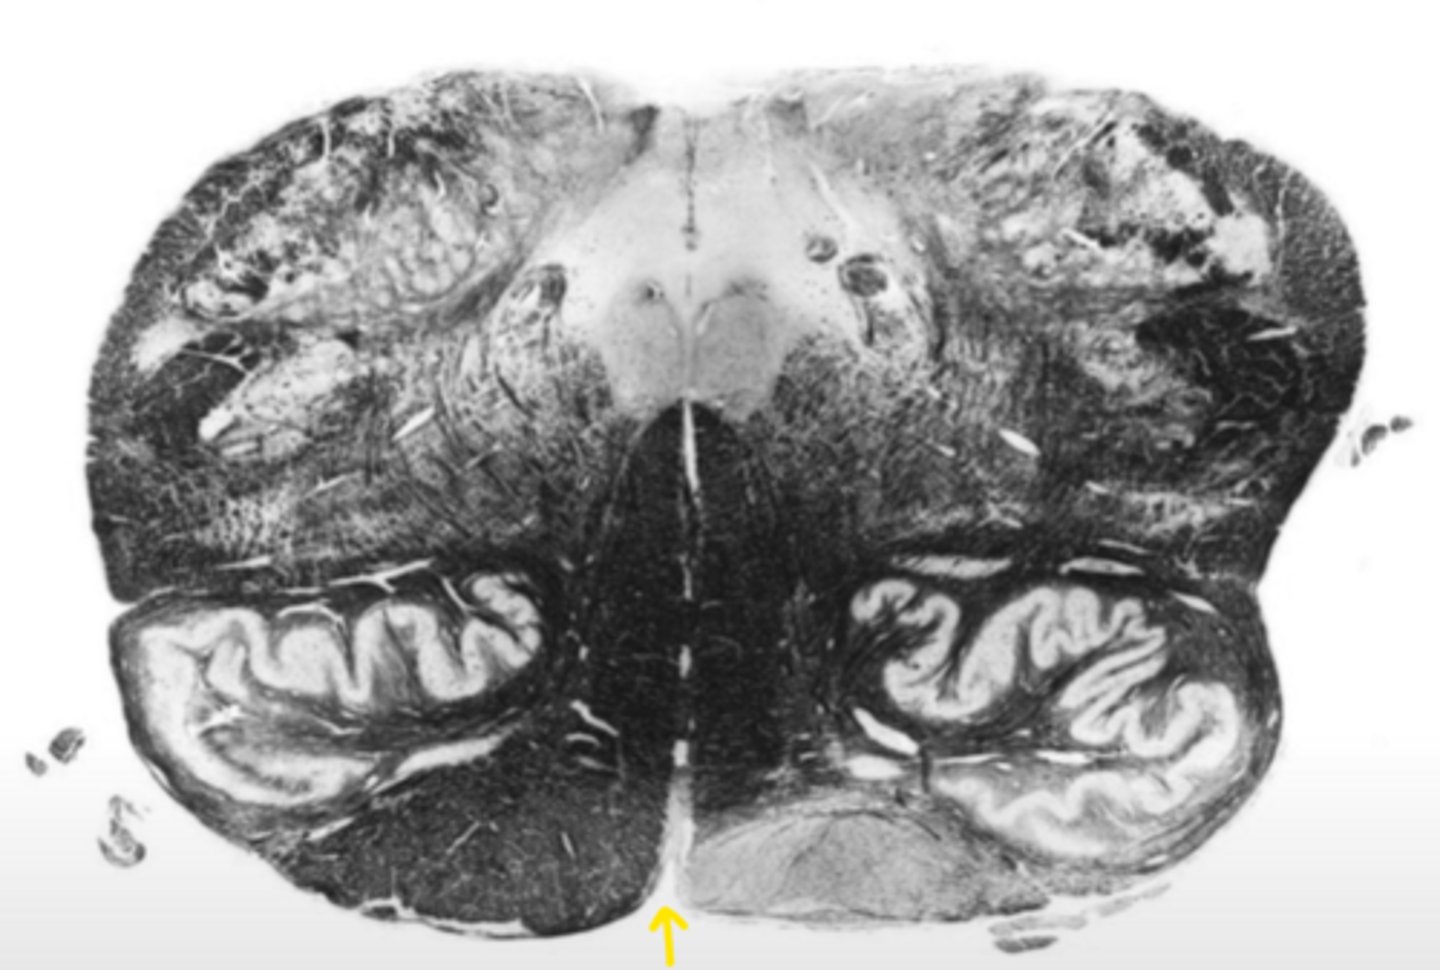

motor decussation

ID the structure

central gray

central canal